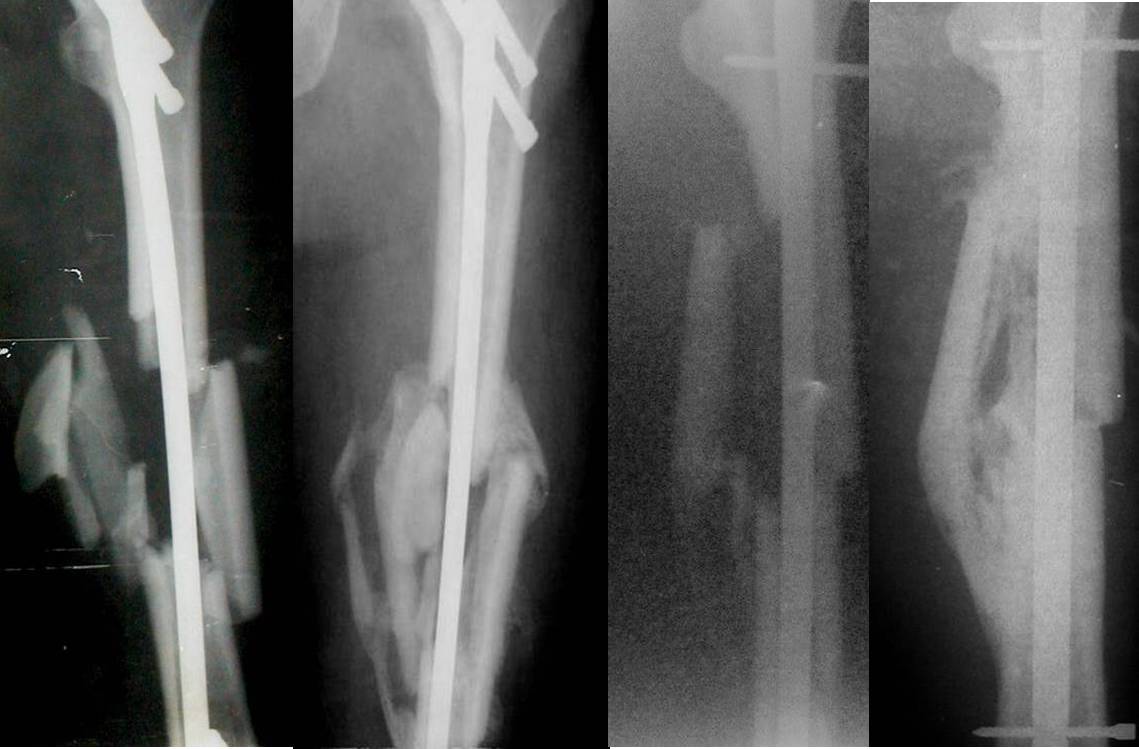

Если выполнено адекватное дистальное и проксимальное блокирование и после операции отсутствует неврологическая или сосудистая симптоматика, нет никакой необходимости что-либо предпринимать ещё. Должно всё срастись без всяких последствий для больного. Примеры во вложенном файле.

Блокирование удалось - почему тогда верхний винт на половину не докручен???

Укорочения нет. Ось восстановлена полностью, блокирование удалось. Единственное - доктор недокрутил статический проксимальный винт, но на прямой проекции он блокирует стержень.

Владимир, вообще-то положено чтобы на рентгенограммах отображались еще и смежные суставы (в данном случае: тазобедренный и коленный)... Ну или хотя бы так, чтобы имплантат был виден весь полностью..... Винт, конечно, докрутить бы надо... А еще проксимальнее есть винт?.... В перелом не лазить!